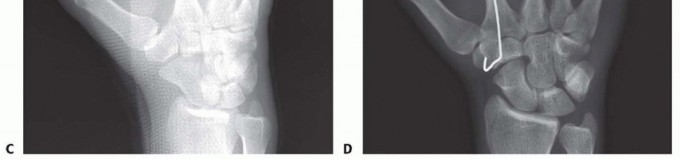

TECH FIG 5 • A,B. Short oblique fracture of the metacarpal. C,D. Fracture stabilized with a lag screw and a neutralization plate. E,F. Short transverse fracture of the second metacarpal stabilized with a compression plate. (C,D: Copyright Thomas R. Hunt III, MD, DSc.)